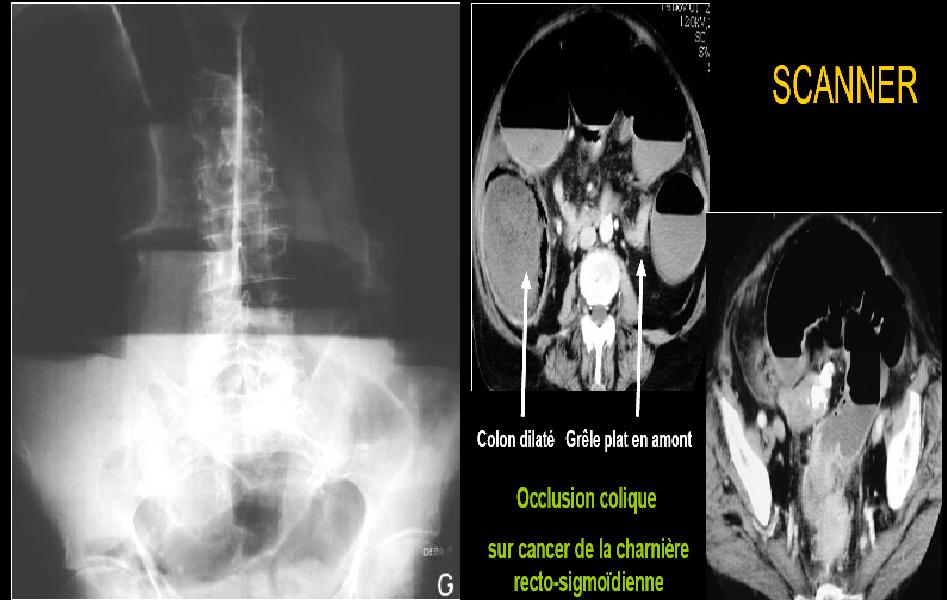

On

suspectera une occlusion colique

sur cancer de la charniere recto-sigmoidienne.

fera un ASP ou l’on verra

au niveau du colon :

-niveaux hydro-aériques périphériques.

-haustrations

épaisses, peu nombreuses.

-plus

hauts que larges.

-peu

nombreux, de grande taille.

Au scanner, on pourra voir un volvulus

soit du caecum ou soit du sigmoide.